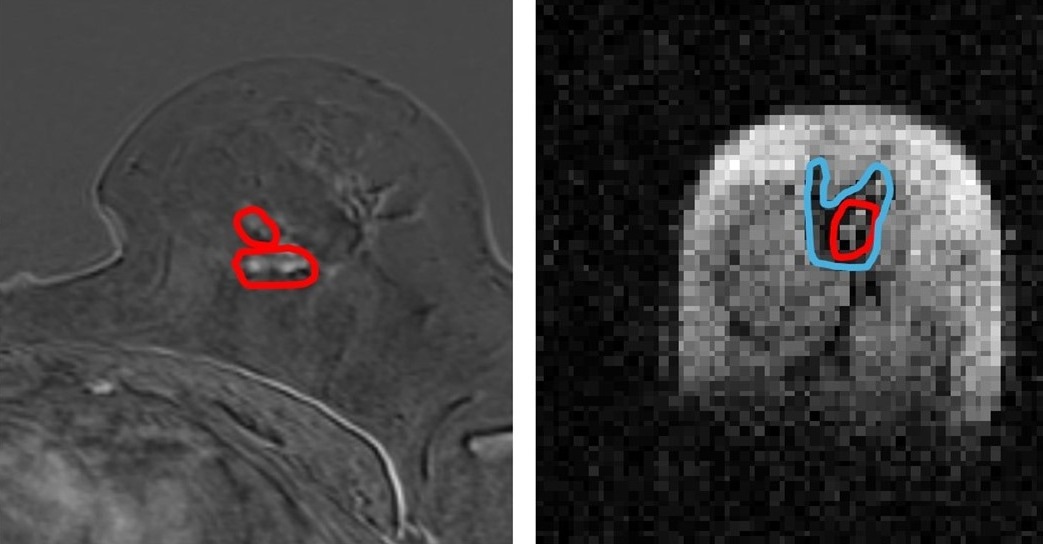

Side by side image of same breast tissue in MRI and FCI. (l) MRI image of breast with cancerous tumours circled in red (r) FCI image of same breast shows same tumour in red with secondary tumour spread in blue. Spread not visible in MRI. The patient had a mixed tumour i.e two different types of tumour and one of them is not visible in MRI. Image Credit: University of Aberdeen

Scientists from the University, in collaboration with NHS Grampian, used a prototype version of the new Field Cycling Imager (FCI) scanner to examine the breast tissue of patients newly diagnosed with cancer. They found that the FCI scanner could distinguish tumor material from healthy tissue with more accuracy than current MRI methods.

This innovation could change the course of treatment for millions of people with cancer. Currently, around 15 percent of women need a second surgery after a lumpectomy as the edges of the tumor may still be involved. This new technique could potentially more accurately outline these tumors and reduce the need for those repeat operations.